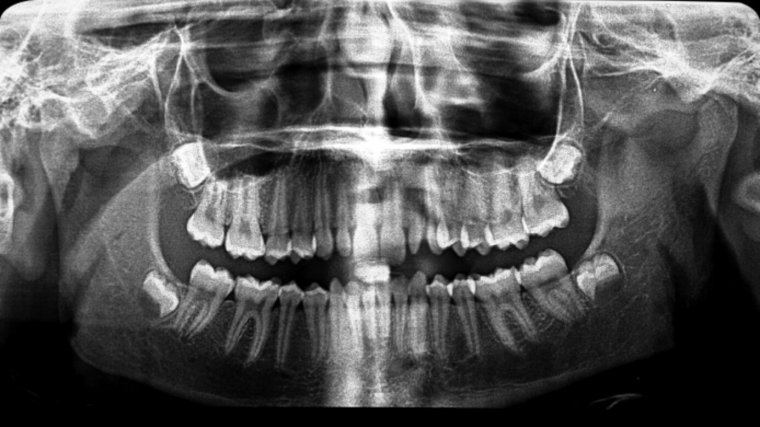

A pesar de que es difícil determinar cuándo existe una alteración, se establece que existe una anomalía cuando la proporción entre los dientes y el maxilar o mandíbula (es decir, la estructura donde se implantan los dientes) no es adecuada.

Las anomalías en tamaño de las piezas dentales son conocidas, según su tamaño, por macrodoncia, dientes más grandes de lo normal, o bien, microdoncia, dientes más pequeños de lo normal, es decir, en relación a la morfología de sus maxilares, su boca y su rostro en general.

La microdoncia se divide en localizada o parcial, y la microdoncia generalizada, según el número de dientes afectados. La más común es la parcial, que se da cuando uno presenta microdoncia solo en algunas piezas en concreto. Normalmente, los dientes más afectados son los incisivos superiores (dientes más anteriores), ya sea uno o los dos.

En el caso de la microdoncia generalizada, todos los dientes presentan un tamaño inferior de lo normal, lo que se puede dar en el enanismo hipofisiario. Un problema distinto, es cuando las piezas son pequeñas en relación al maxilar, debido al gran tamaño de este, y por ello, se aprecian unos dientes pequeños.

La macrodoncia se clasifica según el número de dientes afectados como, parcial o localizada y total. En la macrodoncia parcial, se encuentran afectados determinados dientes, éstos presentan una forma de mayor tamaño y/o con deformidad coronal (parte visible del diente). Los terceros molares inferiores (muelas del juicio inferiores) son los dientes que mayormente presentan macrodoncia. Por otro lado, la macrodoncia generalizada se da cuando se trata de varios dientes que tienen aspecto grande respecto el resto de la dentadura, un hecho que sucede en el gigantismo hipofisiario.